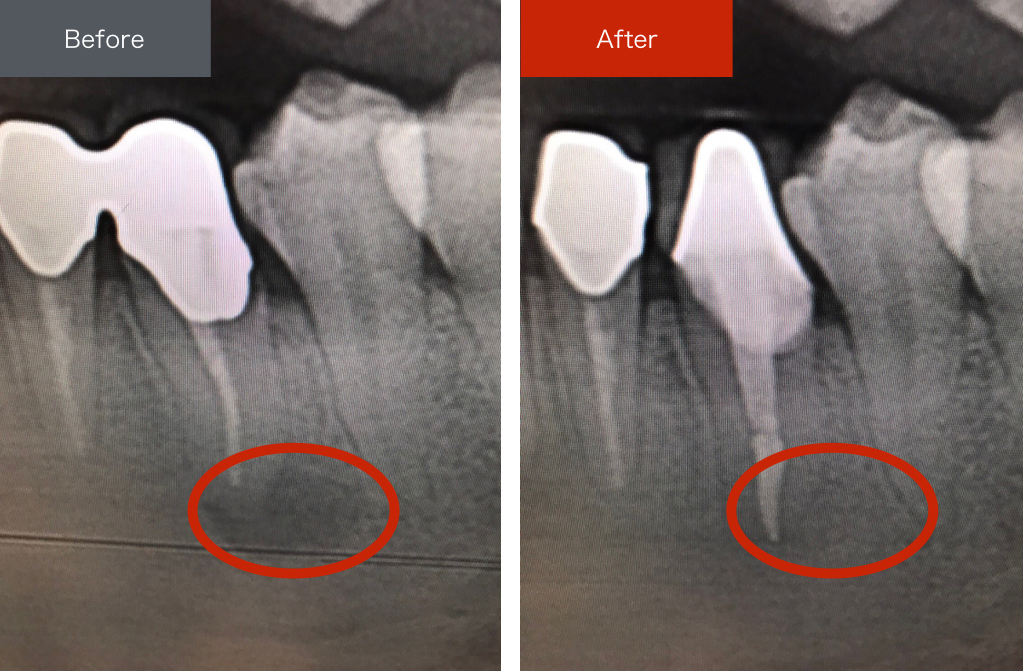

虫歯が神経に到達してしまった場合に必要となる根管治療。抜歯が必要となることが多いこの治療に対し、当院ではマイクロスコープを活用して「残せる歯は完治した状態で残す」ことを目標に精密根管治療を行います。

当院では「膿んでしまって、一度溶けてしまった骨もきちんと再生させるレベル」を完治と言っています。完治を目指す根管治療(根っこの治療)は自費診療になってしまう場合もありますが、大半は保険診療の範囲内で対応可能です。

根管治療は歯を残して被せものをする治療のすべての地盤であり、最も重要な治療です。

この治療がきちんとうまくいってなければ、どんなに綺麗な被せものをいれていても、治療のやりなおしになってしまいます。

また根っこの治療がきちんとできていないと歯は悪化し続けるので、自覚症状がでなくて安心していても、久しぶりに歯医者にいったら、抜歯しなければいけないくらい悪くなっていると診断されてしまうこともあります。

当院では「抜かなくていい歯を抜かない」ために、そして「抜かなくていい歯はしっかりと完治させる」ためにも、しっかりとした根管治療を行ってまいります。